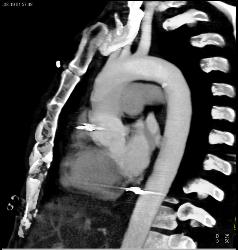

Leak From Descending Aorta